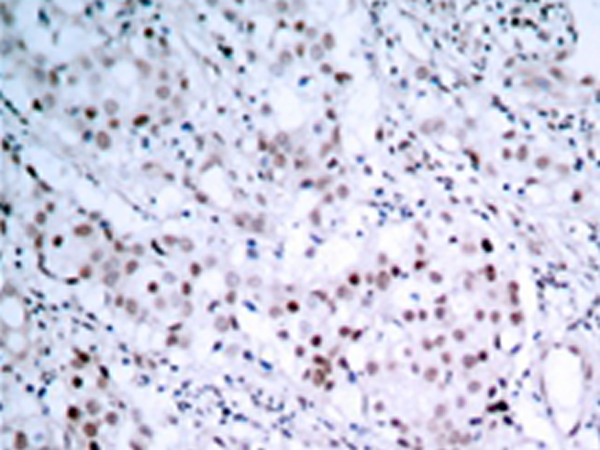

IHC positive control: |

Human breast carcinoma tissue |